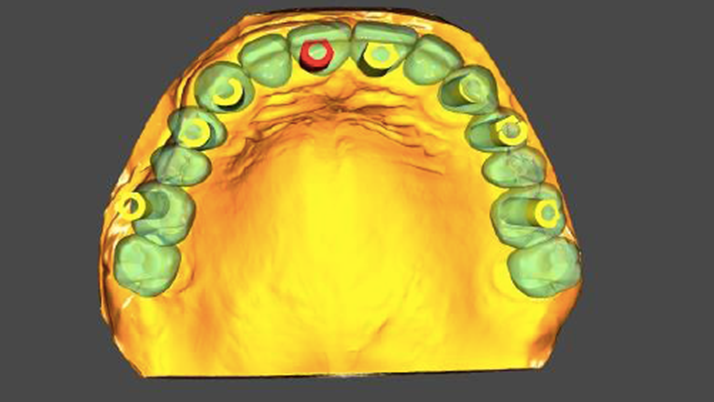

Clinical case: Full-mouth implants for mandibular & maxilla - restored using mixed prostheses

- Courtesy of Dr. Hyun Jun Kim, Korea -

Keywords

AnyRidge, full-mouth implants, mandibular, maxilla, edentulous, full mouth rehabilitation, Octa abutment, long-term clinical case, biological stability, Dr. Hyung Jun Kim